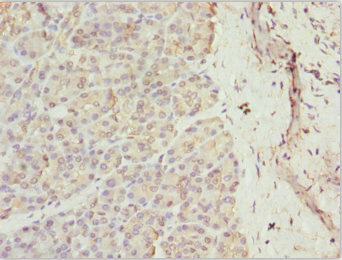

圖片:

應(yīng)用范圍:ELISA, IHC

Application Recommended Dilution IHC 1:20-1:200 -